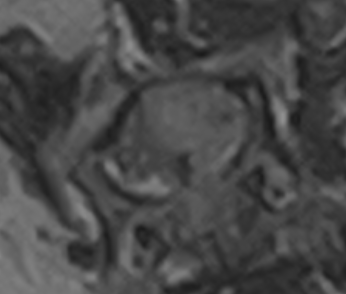

左前肢破行、後肢ふらつきを主訴に来院しました。CT・MRI撮影より、C5-6の椎間板ヘルニア、小脳背側のくも膜下嚢胞が認められました。症状が軽度から中等度、また小脳背側にくも膜下嚢胞が認められ麻酔のリスクなどを考慮し、まずは内科療法から行いました。2か月後症状の改善が認められず、症状も進行し、起立・歩行困難となりました。

左前肢破行、後肢ふらつきを主訴に来院しました。CT・MRI撮影より、C5-6の椎間板ヘルニア、小脳背側のくも膜下嚢胞が認められました。症状が軽度から中等度、また小脳背側にくも膜下嚢胞が認められ麻酔のリスクなどを考慮し、まずは内科療法から行いました。2か月後症状の改善が認められず、症状も進行し、起立・歩行困難となりました。

C5-6椎間板ヘルニア、小脳背側くも膜下嚢胞

C5-6椎間板ヘルニア、くも膜下嚢胞と診断した